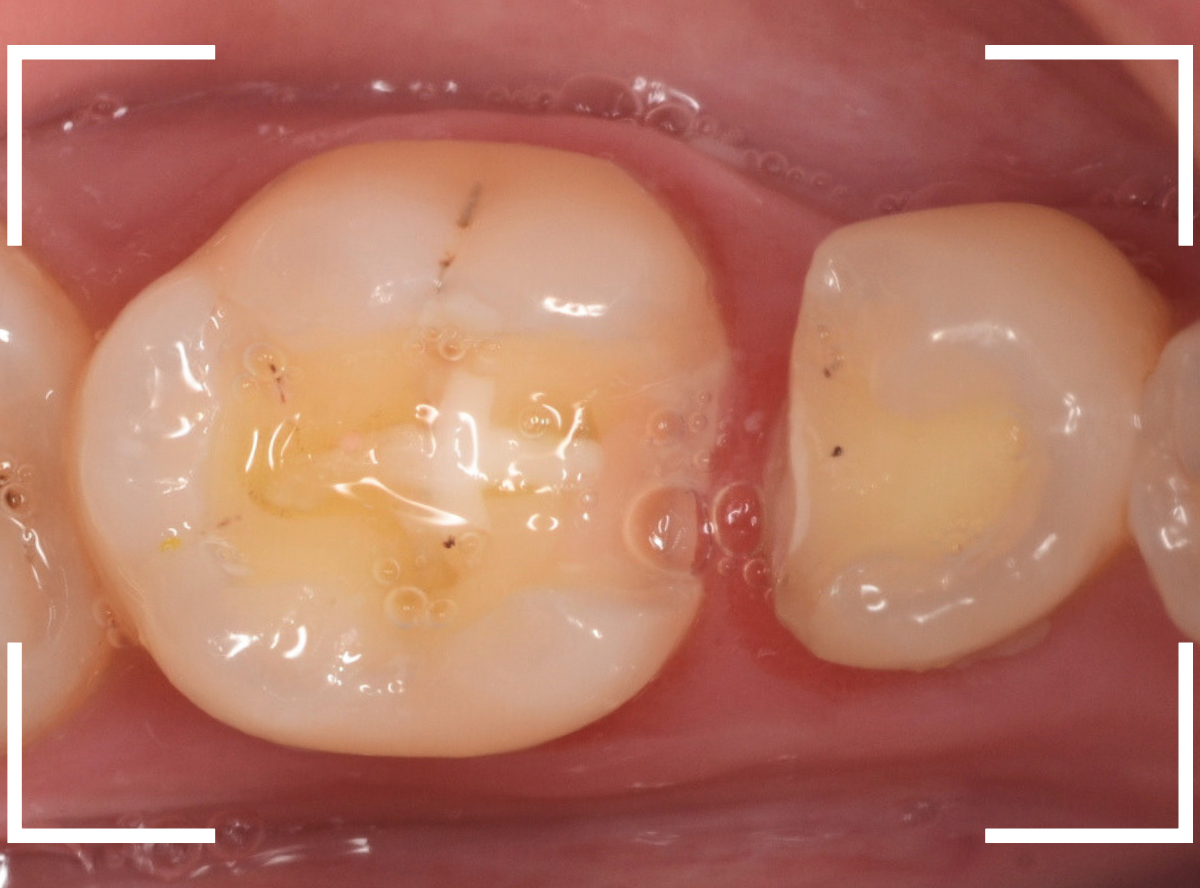

こちらもお薬が入っていますが、外して中を調べます。

こちらは中も問題なかったです。